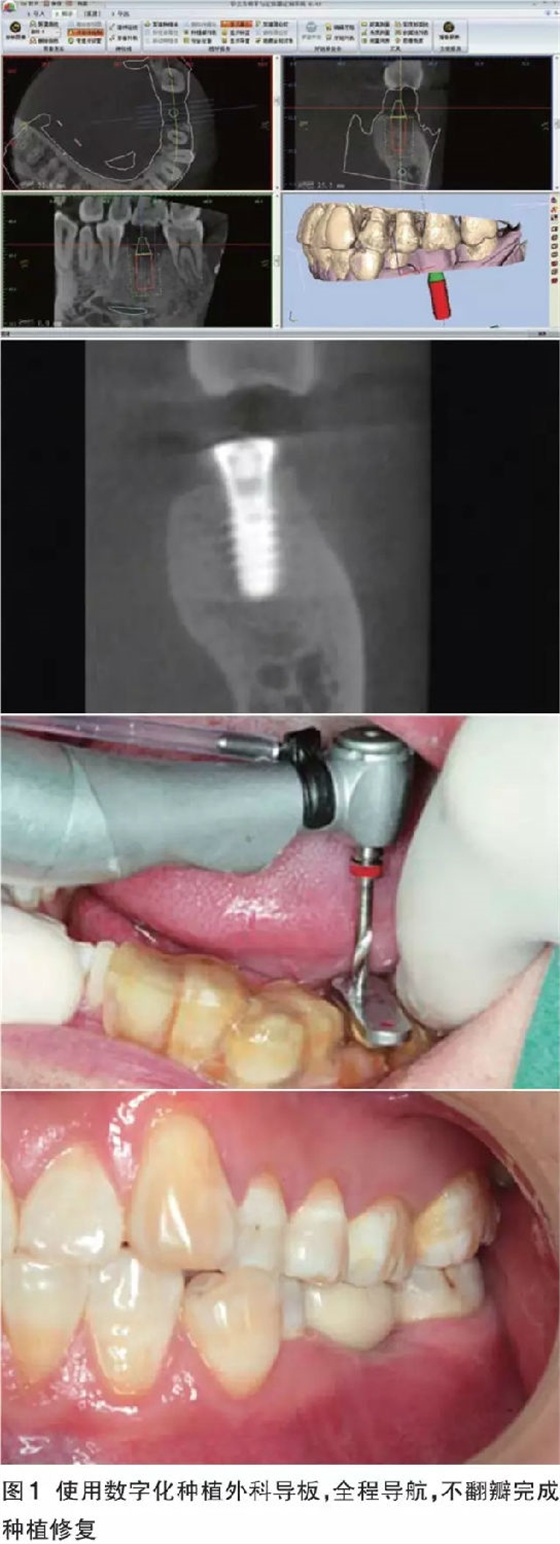

數(shù)字化導(dǎo)板的優(yōu)勢(shì) 對(duì)于軟硬組織充足、解剖條件好,導(dǎo)板能夠容易精準(zhǔn)就位的病例,如果患者經(jīng)濟(jì)條件允許,全套的數(shù)字化解決方案可以預(yù)見性地、完美地、即刻恢復(fù)缺失牙患者的美觀和功能。同時(shí)可以幫助無(wú)經(jīng)驗(yàn)的醫(yī)師規(guī)避重要解剖結(jié)構(gòu)、減少外科風(fēng)險(xiǎn)、獲得術(shù)前根據(jù)修復(fù)效果設(shè)計(jì)的最佳種植體位置(圖1)。